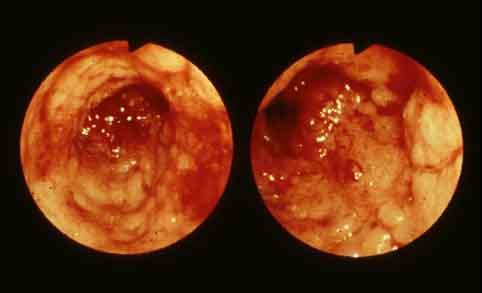

Type 4 (diffusely infiltrating type) advanced colon cancer with long segmental stenosis from the rectum to the sigmoid colon.

Malignant epithelial tumor/Adenocarcinoma

Large intestine(Colon)/Rectum

Endoscopy

Type 4 Diffusely infiltrating type/

40 -